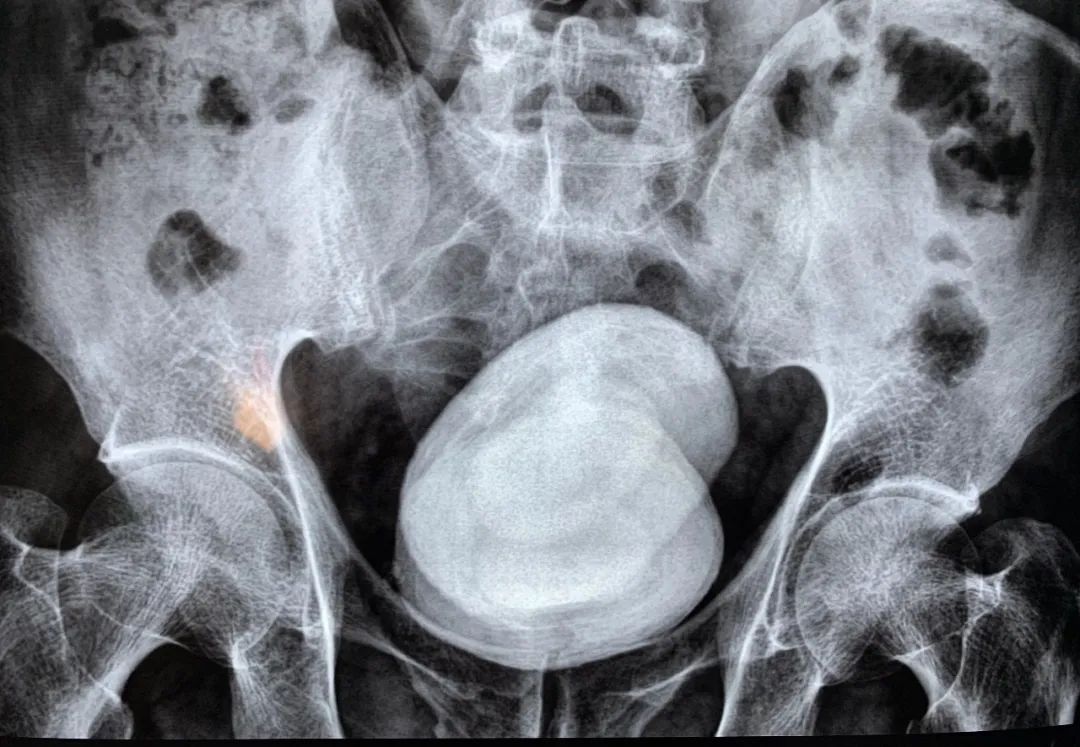

可能会出现尿频、尿急、尿痛、排尿不畅等尿路刺激症状,可伴随小腹及膀胱区疼痛,主要是由于膀胱结石刺激膀胱逼尿肌收缩所导致。

因为结石在膀胱内活动,对膀胱黏膜造成损伤,进而引起表面毛细血管破裂出血,所以还可能出现血尿的情况。